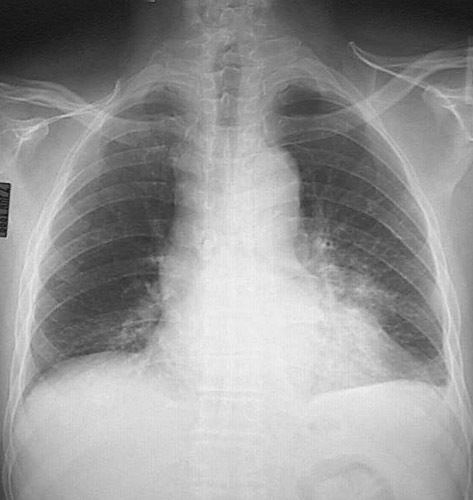

This chest radiograph reveals widening of the mediastinum with prominent right as well as left border because of marked lymphadenopathy in a patient with metastases. The primary (a peripheral adenocarcinoma) is hiding in an infiltrate.